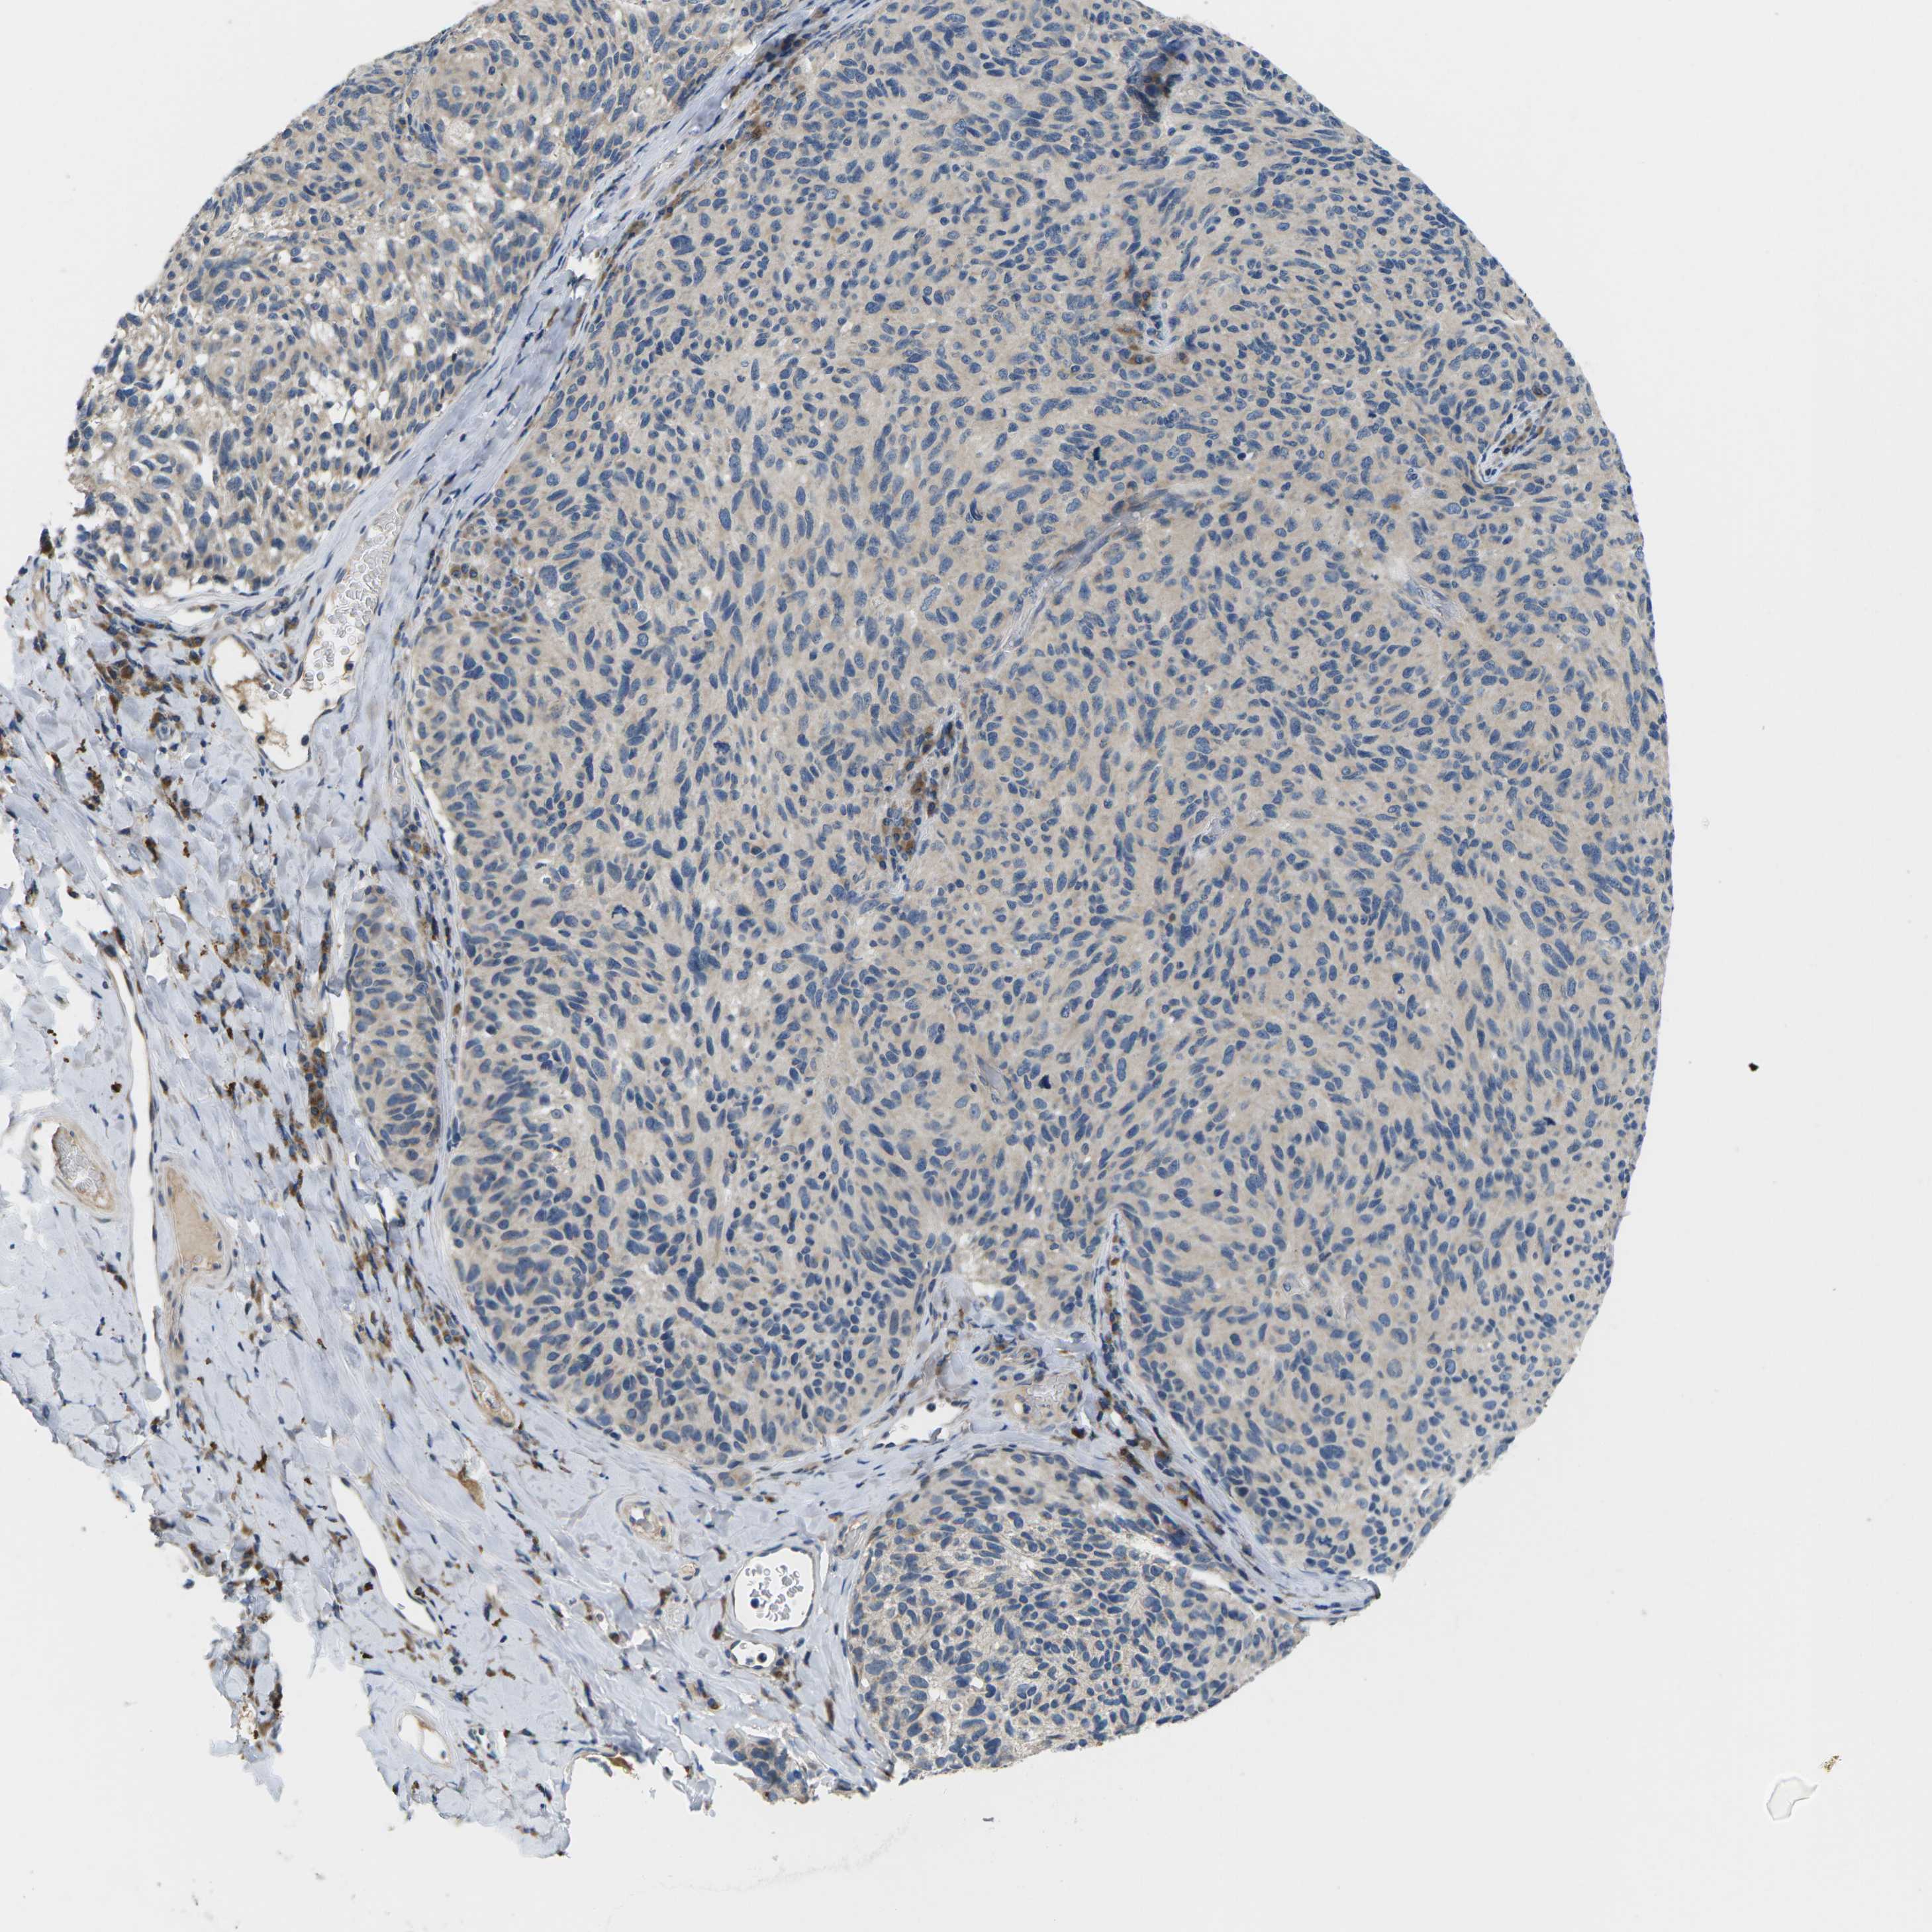

MELANOMA - Protein expressioni

A mouse-over function shows sample information and annotation data. Click on an image to view it in a full screen mode. Samples can be filtered based on level of antibody staining by selecting one or several of the following categories: high, medium, low and not detected. The assay and annotation is described here.

Note that samples used for immunohistochemistry by the Human Protein Atlas do not correspond to samples in the TCGA dataset.

Antibody stainingi

Antibody staining in the annotated cell types in the current human tissue is reported as not detected, low, medium, or high, based on conventional immunohistochemistry profiling in selected tissues. This score is based on the combination of the staining intensity and fraction of stained cells.

Each image is clickable and will lead to virtual microscopy that enables deeper exploration of all samples and also displays staining intensity scores, fraction scores and subcellular localization as well as patient and tissue information for each sample.

Antibody HPA015242

Antibody HPA015968

Staining

High

Medium

Low

Not detected

Intensity

Strong

Moderate

Weak

Negative

Quantity

>75%

75%-25%

<25%

None

Location

Nuclear

Cytoplasmic/membranous

Cytoplasmic/membranous,nuclear

Malignant melanoma, NOS

Malignant melanoma, Metastatic site